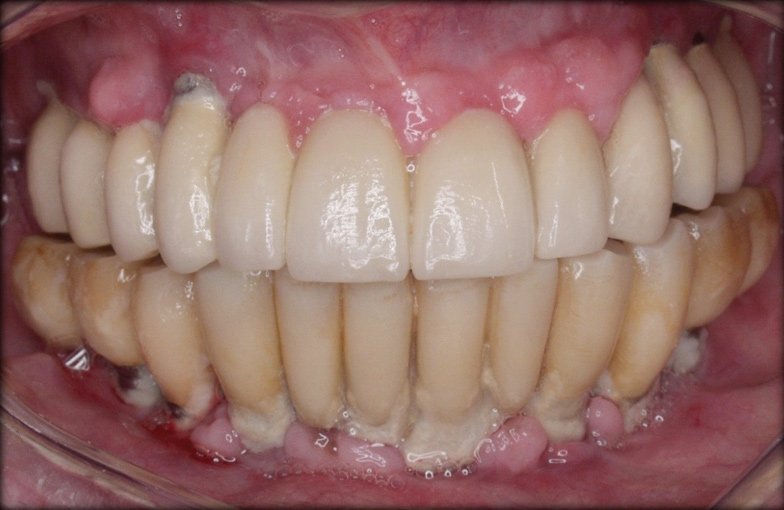

Preventive protocols must be instituted immediately after the installation of the definitive prosthesis and must focus on the importance of plaque control, both patient self-plaque control by strict home-based oral-hygiene practices and professional mechanical biofilm debridement at regular professional interventions, which must be customized to the patient’s risk profile.8 The efficacy of oral hygiene practices will depend on the ease of access to plaque control with both dental brushes and interdental devices, which depends mainly on the design of the prosthesis (Figure 6 through Figure 8). A cleansable implant-supported restoration, therefore, becomes a key factor in the primary prevention of peri-implant diseases. A recent systematic review on the efficacy of mechanical self-performed oral hygiene of implant-supported restorations reported a slight trend of superiority with the use of powered toothbrushes compared with manual.14

Fig 6. Customized oral hygiene to the implant-supported restoration with use of interdental brush;

Figure 6

Fig 7. use of gauze under the pontic.

Figure 7

Fig 8. use of gauze at the interdental space.

Figure 8